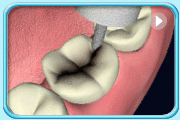

动画所见是以牙科工具清除臼齿的蛀坏部分,并以汞合金填补蛀洞的过程。